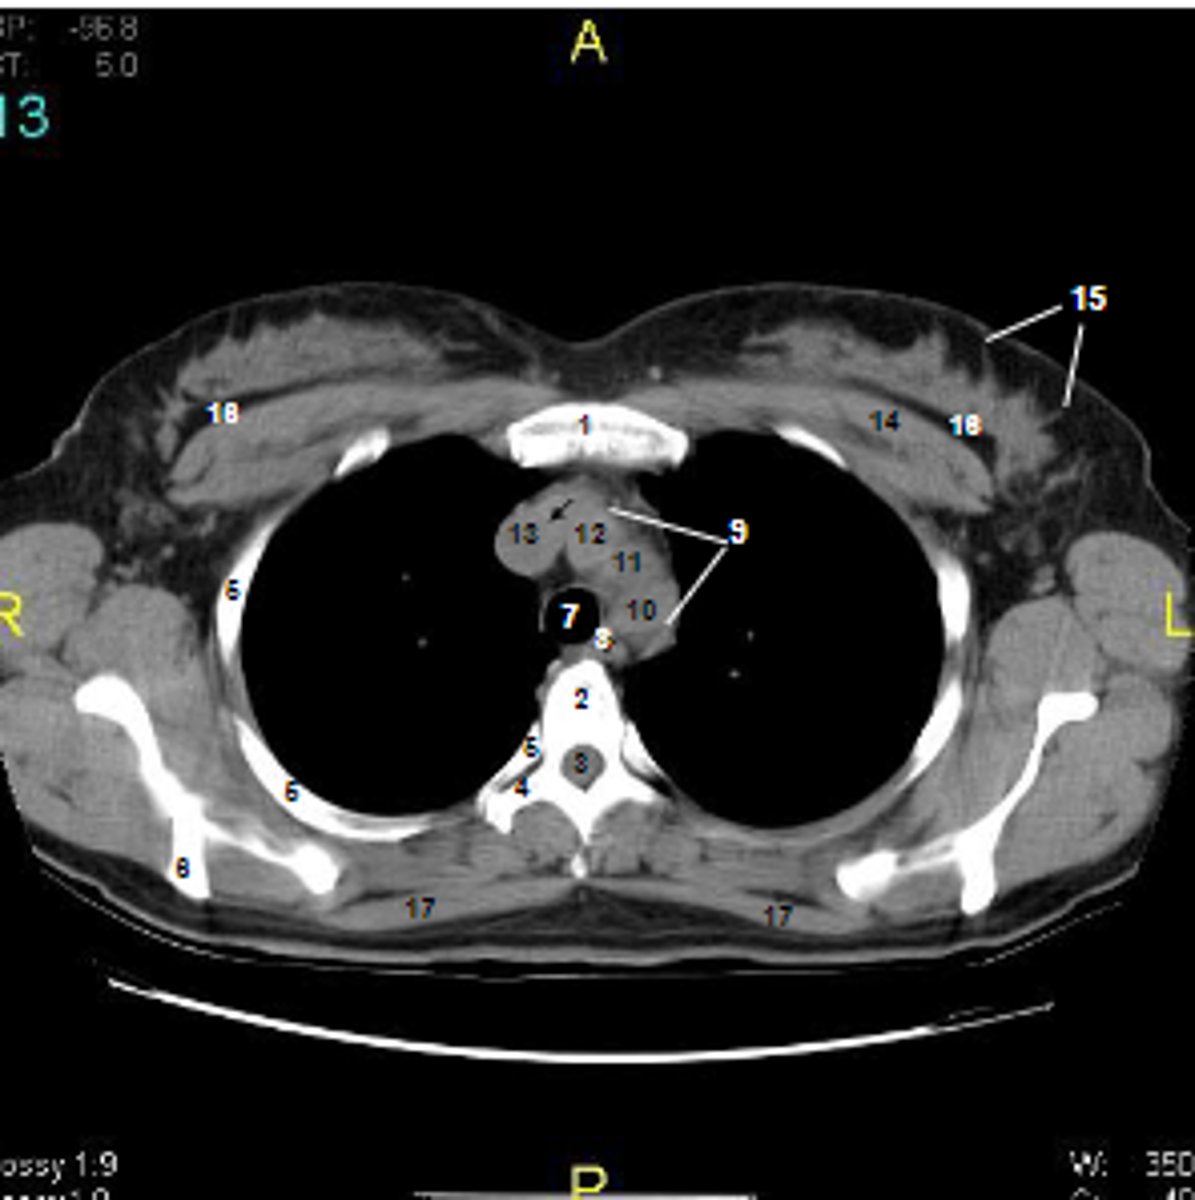

1

at what number is the sternum

2

at what number is the vertebral body

3

at what number is the vertebral canal/ spinal cord

4

at what number is the transverse process of vertebra

5

at what number is the rib

6

at what number is the spine of scapula

7

at what number is the trachea

8

at what number is the esophagus

9

at what number is the arch of aorta

10

at what number is the left subclavian artery

11

at what number is the common carotid artery

12

at what number is the brachiocephalic trunk

13

at what number is the superior vena cava

14

at what number is pectoralis major

15

at what number are Cooper's ligaments

16

at what number is the retromammary space

17

at what number is trapezius